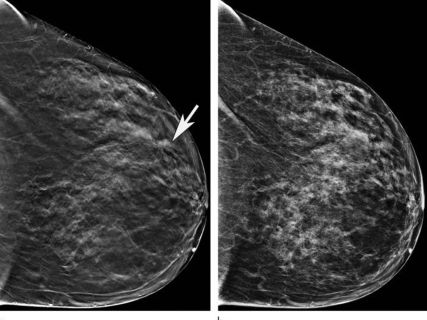

Almudena Quintana Morgado, directora general Asistencial del Servicio Madrileño de Salud (Sermas), ha asegurado la eficiencia del Programa de Detección Precoz del Cáncer de Mama (DEPRECAM) en Madrid, destacando que no hay listas de espera estructurales y que el tiempo medio de espera es de 34 días para realizar una mamografía, garantizando además que todas las pacientes son informadas sobre los resultados de sus pruebas.

Durante 2023, el programa ha detectado 2.576 casos sospechosos de cáncer, requiriendo pruebas adicionales para confirmar el diagnóstico. Además, la tasa de detección de cáncer está en 5,4 casos por cada mil mujeres examinadas, con un alto porcentaje de detección en estadios iniciales, lo que facilita tratamientos menos invasivos y mejora las tasas de curación.